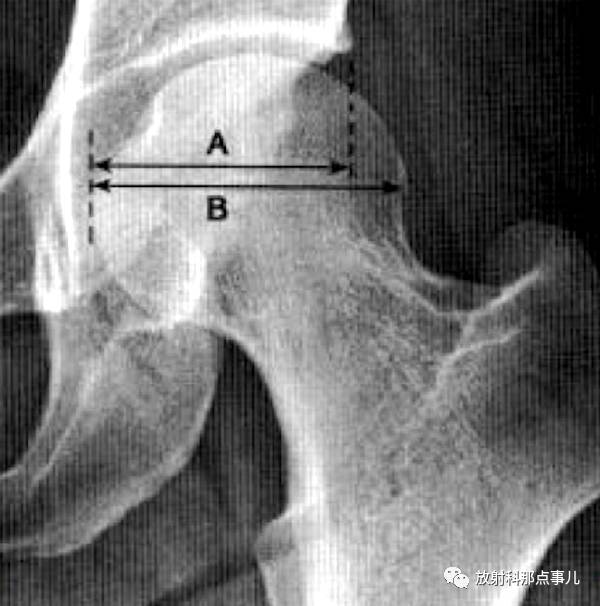

髋臼覆盖率

股骨头受髋臼覆盖部分的横径除以股骨头的横径,正常时应大于0.75。用于判断股骨头移位情况。

骨骺指数、骨骺商

骨骺指数,在髋关节正位片上,分别测量股骨头骨骺的高度和骨骺的宽度,将骨骺高度除以骨骺的宽度X100即为骨骺指数。该指数表示股骨头骨骺变扁的程度,用于评价Pathe并及发育性髋关节脱位的治疗效果。

骨骺商,指患侧骨骺指数除以健侧骨骺指数。骨骺商计算主要用于与健侧对比以判断病变程度及治疗效果。